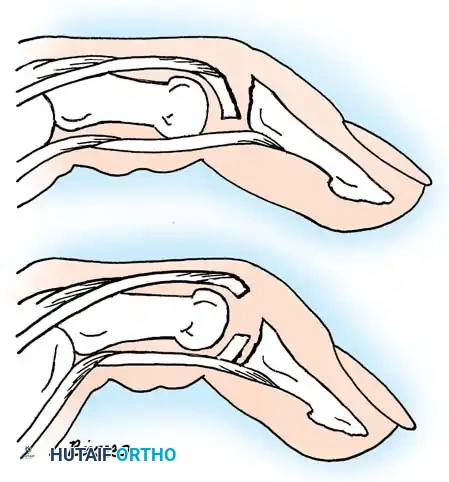

While simple dislocations of the metacarpophalangeal (MCP) joint can be reduced closed, complex dislocations require open intervention.

Image

As described by Farabeuf, McLaughlin, and Green, a complex dislocation occurs when the volar plate ruptures proximally and becomes interposed in the joint space. The metacarpal head is driven volarly and becomes trapped in a tight soft-tissue noose. This noose is formed by the volar plate dorsally, the flexor pollicis brevis (FPB) radially, the adductor pollicis ulnarly, and the displaced flexor pollicis longus (FPL) tendon.

Traction exacerbates the noose effect. Open reduction, typically via a volar approach, is required to incise the A1 pulley, retract the tendons, and extract the volar plate from the joint space, allowing the metacarpal head to be reduced.